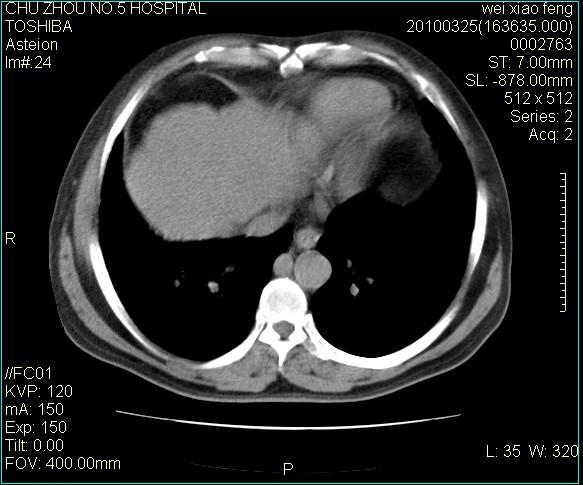

男,60岁,反复咳、痰、喘3月,加重3天。

心功能怎么样?感觉象肺淤血。

右肺中叶结节影为原发灶,考虑右肺中叶周围型肺癌并淋巴道转移